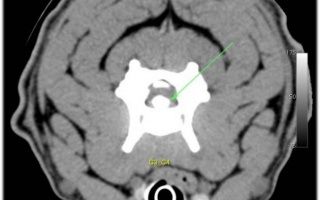

Notre équipe prend en charge les affections du cerveau et de la colonne (hernies discales, instabilités cervicales, tumeurs, traumatismes) du diagnostic rapide à l’intervention.

Chaque dossier est préparé par IRM/Scanner, discuté en collégial et opéré sous monitoring anesthésique strict. Objectif : décomprimer, soulager la douleur et restaurer la mobilité, avec hospitalisation en soins intensifs si nécessaire.

Consultations de neurologie

- Scanner

- IRM

Chirurgie de la colonne vertébrale

- Hernies discales

Chirurgie du crâne

- Méningiomes

- Hydrocéphalie

- Syringomélie